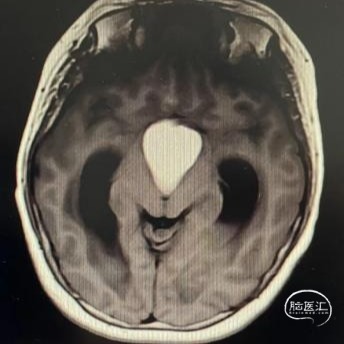

头部MRI显示:鞍区-鞍上区-第三脑室可见一不规则囊状长T1极长T2信号灶,大小约43mm*32mm*43mm,增强后可见病灶不均匀明显强化。垂体及视交叉未见显示,双侧脑室扩张,双侧脑室旁可见对称性斑片状长T1长T2信号灶。